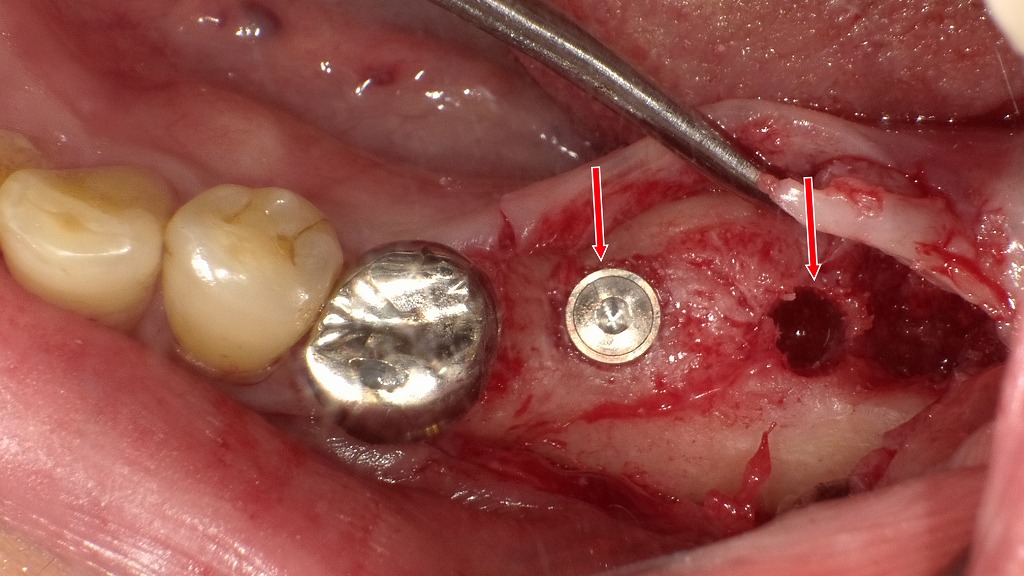

この画像は、前回の症例(左下6番・7番欠損部)に対するインプラント埋入手術中の様子を示しています。以下に詳細を解説します。

🦷 術中の所見

- 左下6番部(中央の赤矢印)

インプラント体の埋入が完了しています。

トルク値や初期固定も良好で、カバースクリューが装着されている状態です。

周囲骨の切削面も安定しており、骨質は緻密で十分な支持が得られています。 - 左下7番部(右側の赤矢印)

ドリリング(骨形成)が完了した段階です。

これからインプラント体を埋入する予定の位置が確認できます。

出血状態や骨の色調から判断して、骨量・骨質ともに十分で、追加の骨造成は不要と考えられます。 - 左下5番部(金属冠)

既存の補綴物が隣接しており、埋入ポジションのガイドとして利用されています。

🔩 手術の概要

- 手術部位:左下6・7番部

- 術式:2回法インプラント埋入手術

- 内容:

- フラップを開けて骨面を露出

- 6番部にインプラント体を埋入

- 7番部はドリリング完了後に埋入予定

- 縫合後、一次治癒を待って二次手術へ進む計画

💡 コメント・所見

- 骨吸収は軽度で、骨幅・高さともに良好。

- 神経管までの距離も十分に確保されています。

- 術野の出血もコントロールされ、手技はクリーンに行われています。